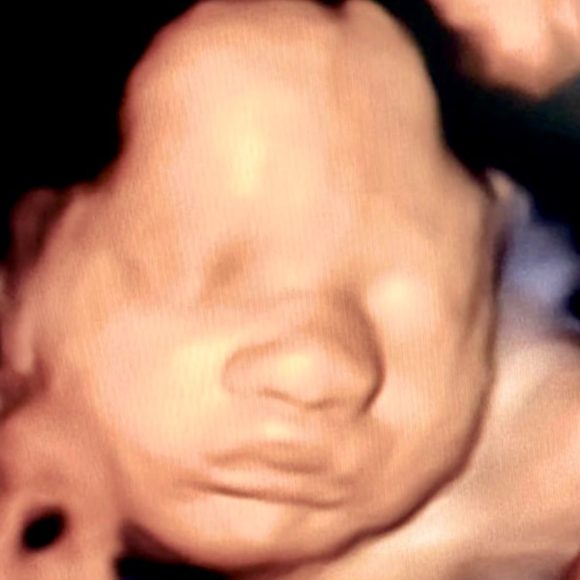

Perinatoloji, gebelik öncesi, gebelik süreci ve doğum sonrası dönemde anne ve bebeğin sağlığını en üst düzeyde korumayı amaçlayan bir tıp dalıdır. Bu alan özellikle yüksek riskli gebeliklerin takibi, prenatal tanı ve tedavi süreçlerini kapsar. Gebelikte oluşabilecek komplikasyonları önceden tespit etmek ve en doğru yaklaşımları belirlemek için perinatoloji uzmanlarının desteği büyük önem taşır.